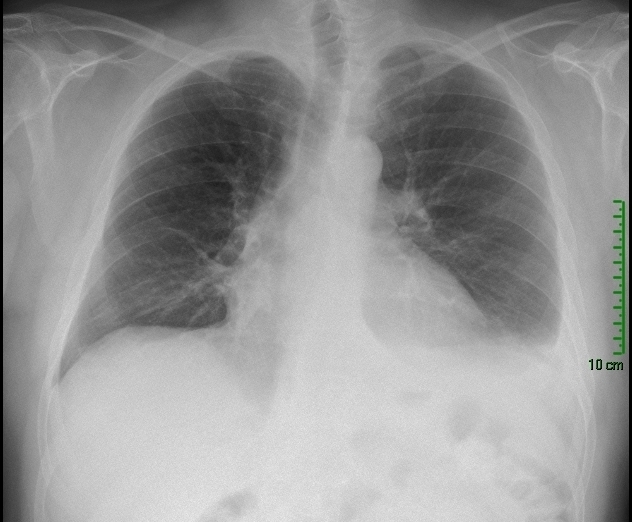

À l’examen clinique : pression artérielle 129/62 mmHg ; fréquence cardiaque 106/m ; SpO2 90 % en air ambiant ; température 37,6 °C ; fréquence respiratoire 26/m. Les bruits du cœur sont réguliers sans bruit surajouté, l’auscultation pulmonaire est claire, il n’y a pas de signes de détresse respiratoire aiguë, et l’examen neurologique est sans particularité.

L’absence de crépitant rend ce diagnostic improbable (un œdème aigu du poumon [OAP] peut rarement avoir une auscultation normale initialement, mais ici la dyspnée évolue depuis plus de 24 heures).

Bien qu’un pneumothorax de faible/moyenne importance puisse être manqué à l’auscultation, le tableau de désaturation profonde présenté par la patiente ne serait compatible qu’avec un pneumothorax complet voire compressif, qui devrait être perçu à l’auscultation.

L’absence de sibilant rend ce diagnostic très improbable. En cas d’asthme aigu grave particulièrement sévère, ceux-ci peuvent manquer mais il s’agit dans ce cas d’un silence auscultatoire.

La tamponnade peut provoquer une dyspnée avec désaturation avec auscultation normale (en dehors de la tachycardie), le frottement péricardique étant assez inconstant et plus volontiers présent en cas d’épanchement de faible abondance.